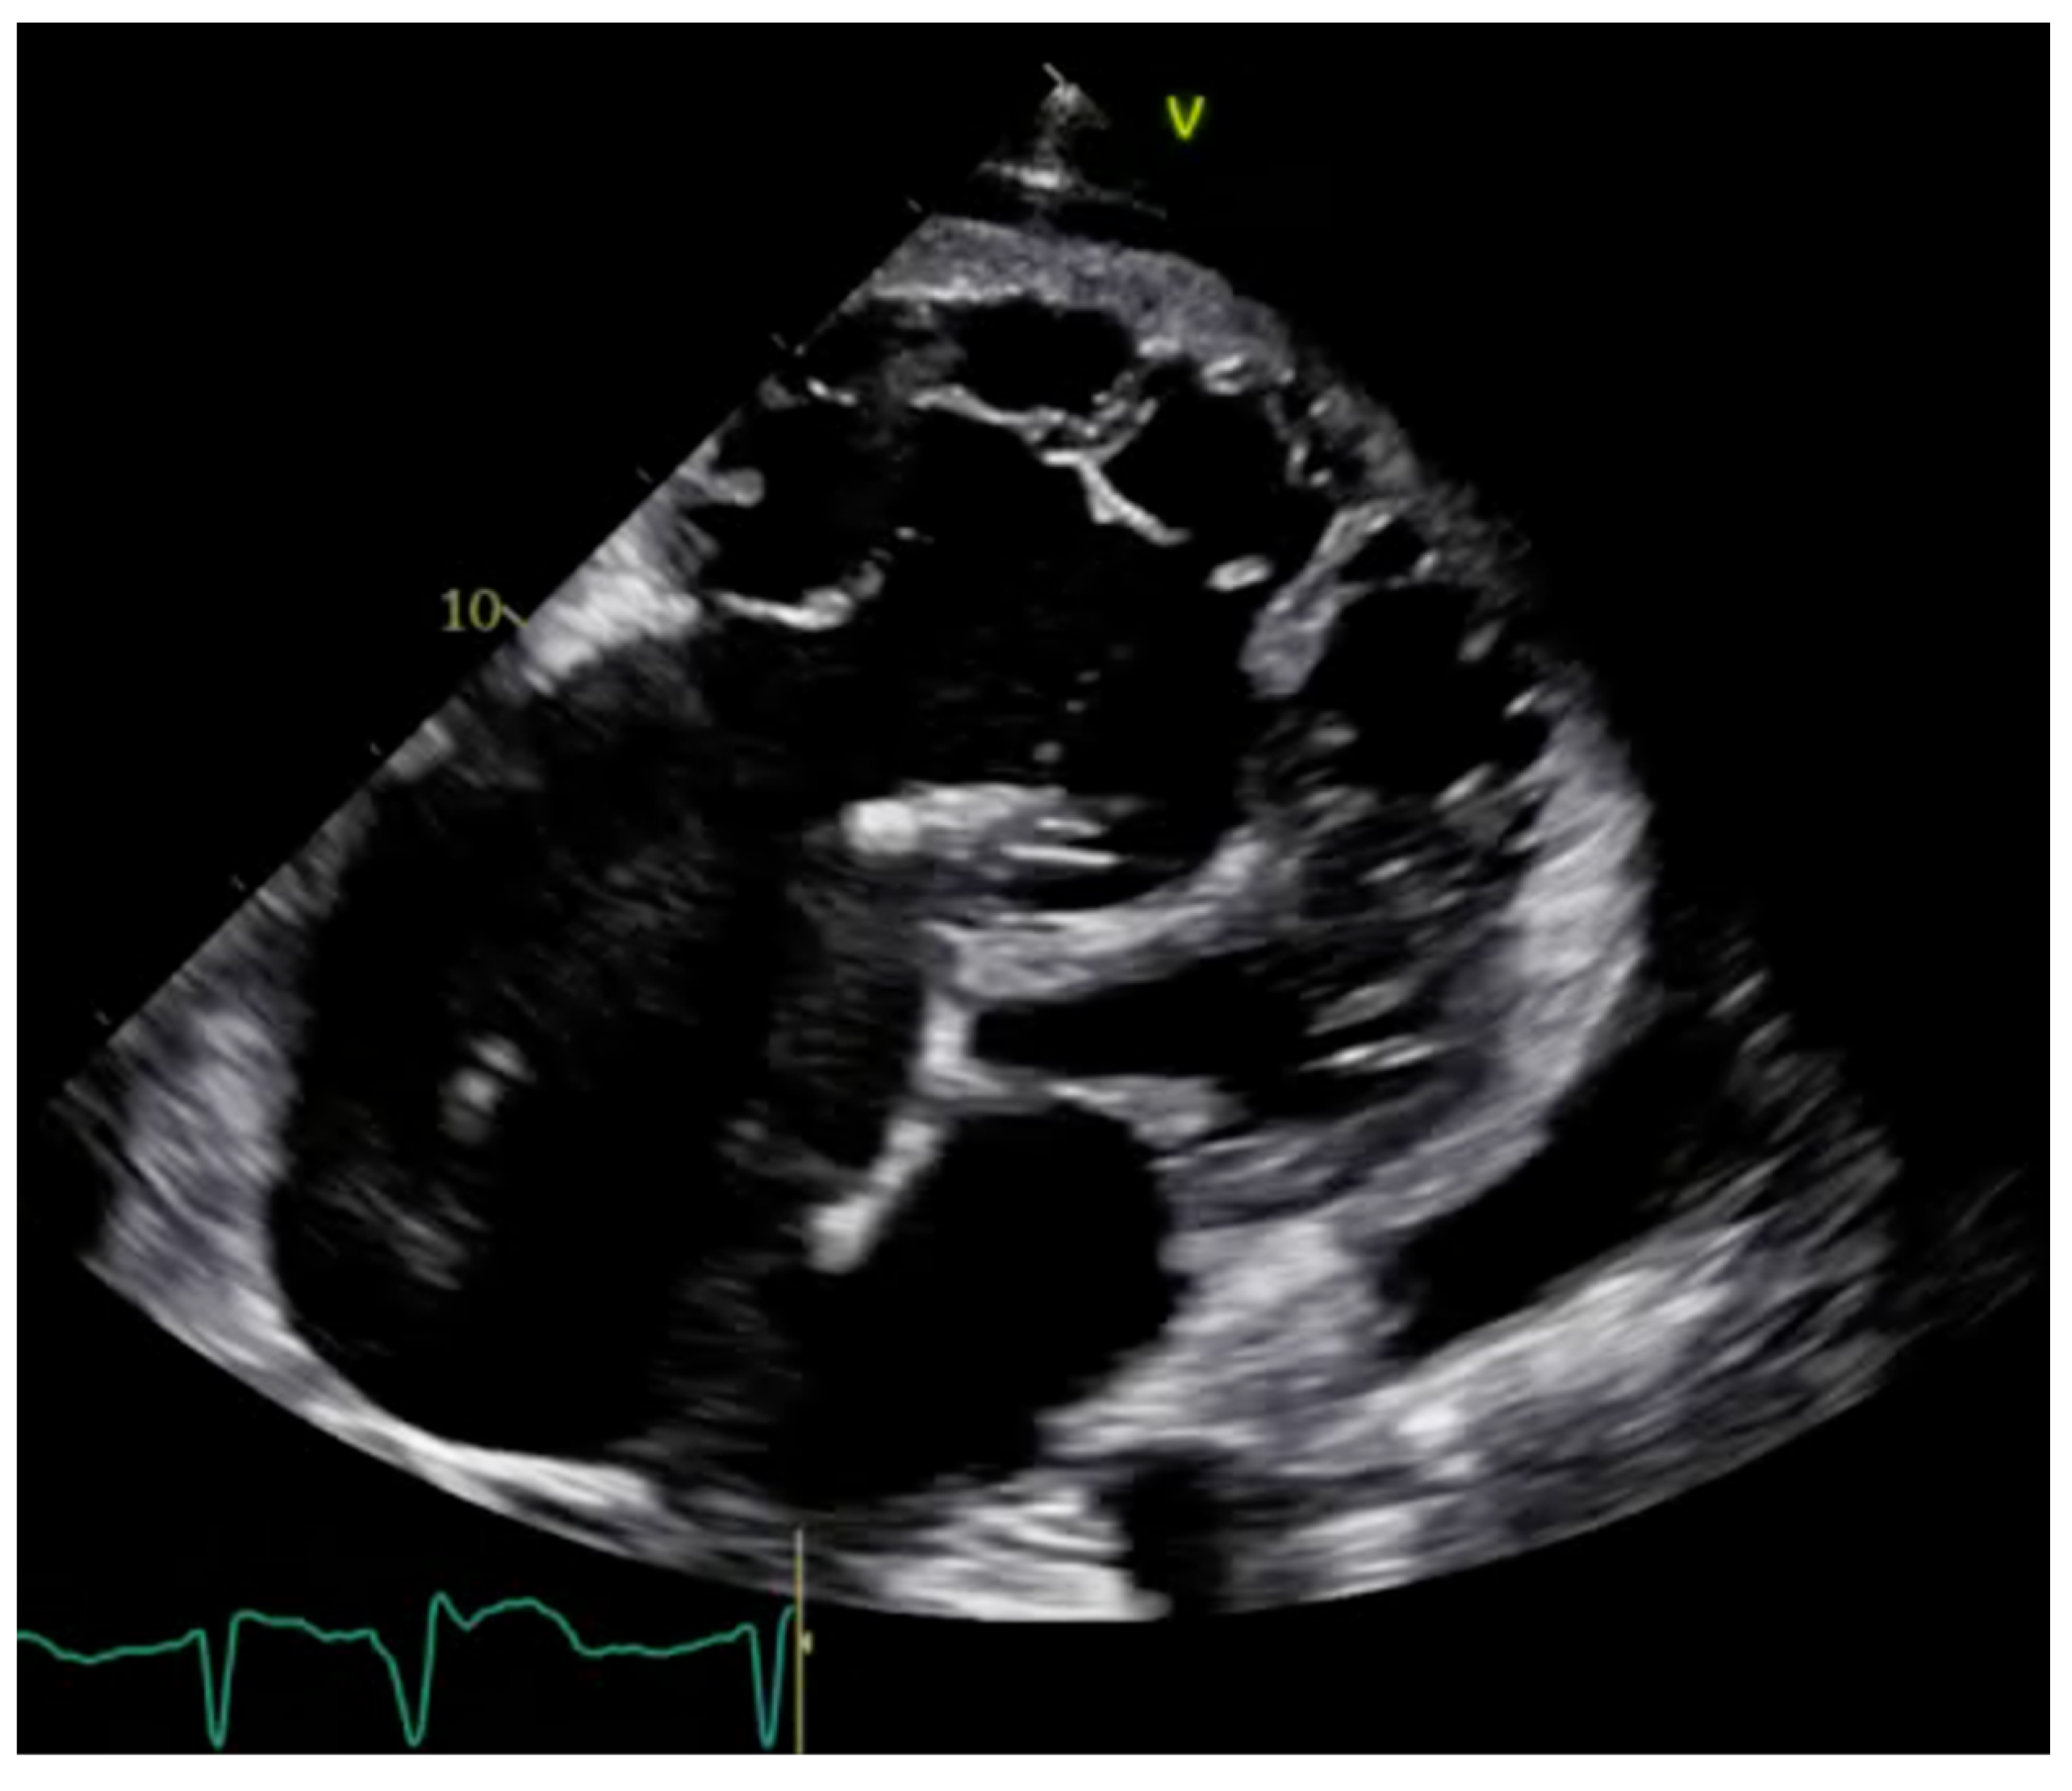

2.1. Echocardiography: The First Line of Diagnosis